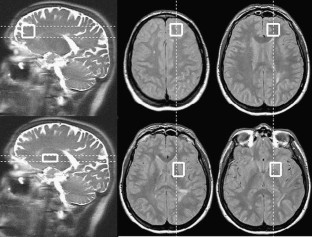

Included in the study were 41 patients with relapsing–remitting MS with mild disability and 20 healthy controls. Fatigue was assessed by the Fatigue Severity Scale (FSS) and the Modified Fatigue Impact Scale (MFIS). Patients were classified as “fatigued” when they expressed a subjective feeling of fatigue, and the FSS score was ≥5.0 and/or the MFIS score was >38. Patients with no subjective fatigue were classified as “nonfatigued” when the FSS score was <4.0. Proton magnetic resonance spectra were obtained from two different regions: the frontal white matter and the lentiform nucleus. The relationships between fatigue and NAA/Cr, NAA/Cho and Cho/Cr ratios were analysed.

Fig. 1